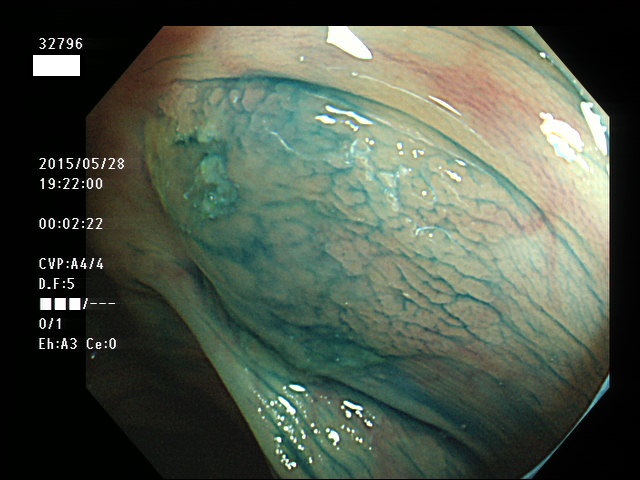

上記100名より抽出した平坦・陥凹型腺腫(=癌化の危険が高いが見落としやすい病変)の内視鏡写真

腺腫発見率 57% (カルテ番号32700〜32799の100名の方の検査結果で集計)

以下のカルテ番号の方に腺腫(Adenoma,Group3〜5)が見つかりました

32784 32787 32788 32790 32794 32795 32796 32798 32799・・・・・・の57名